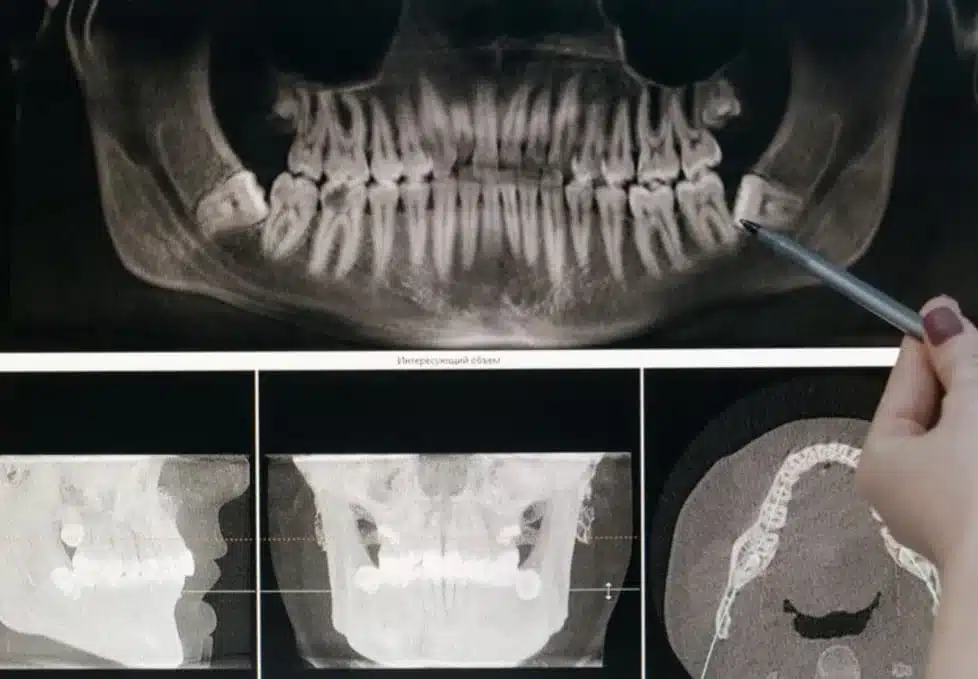

Advanced Technology and Sedation Options

We combine advanced technology with sedation options to ensure that every procedure is as comfortable and efficient as possible. From diagnosis to recovery, our goal is to provide exceptional outcomes that improve both oral health and quality of life.